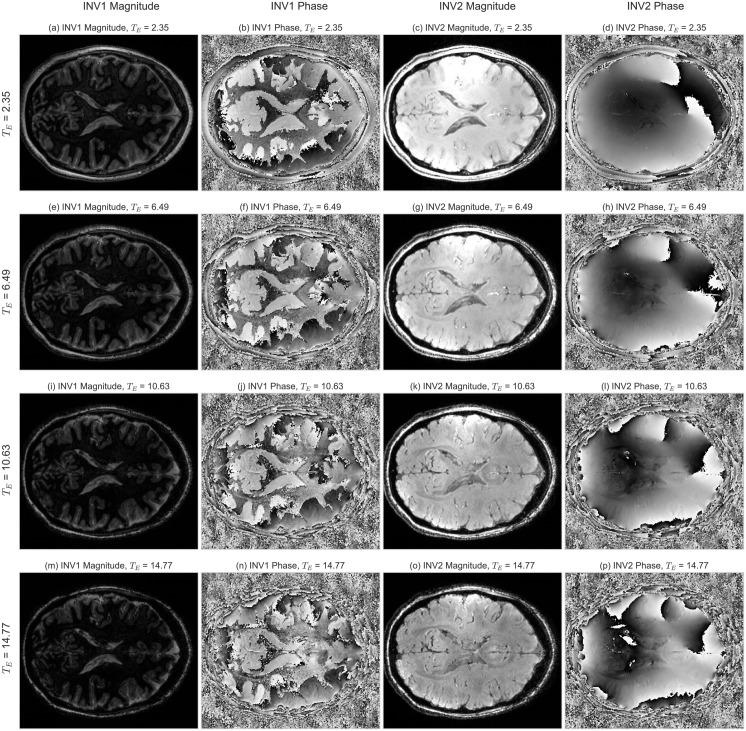

Simultaneous Quantitative MRI Mapping of T1, T2* and Magnetic Susceptibility with Multi-Echo MP2RAGE.

The knowledge of relaxation times is essential for understanding the biophysical mechanisms underlying contrast in magnetic resonance imaging. Quantitative experiments, while offering major advantages in terms of reproducibility, may benefit from simultaneous acquisitions. In this work, we demonstrate the possibility of simultaneously recording relaxation-time and susceptibility maps with a prototype Multi-Echo (ME) Magnetization-Prepared 2 RApid Gradient Echoes (MP2RAGE) sequence. T1 maps can be obtained using the MP2RAGE sequence, which is relatively insensitive to inhomogeneities of the radio-frequency transmit field, [Formula: see text]. As an extension, multiple gradient echoes can be acquired in each of the MP2RAGE readout blocks, which permits the calculation of [Formula: see text] and susceptibility maps. We used computer simulations to explore the effects of the parameters on the precision and accuracy of the mapping. In vivo parameter maps up to 0.6 mm nominal resolution were acquired at 7 T in 19 healthy volunteers. Voxel-by-voxel correlations and the test-retest reproducibility were used to assess the reliability of the results. When using optimized paramenters, T1 maps obtained with ME-MP2RAGE and standard MP2RAGE showed excellent agreement for the whole range of values found in brain tissues. Simultaneously obtained [Formula: see text] and susceptibility maps were of comparable quality as Fast Low-Angle SHot (FLASH) results. The acquisition times were more favorable for the ME-MP2RAGE (≈ 19 min) sequence as opposed to the sum of MP2RAGE (≈ 12 min) and FLASH (≈ 10 min) acquisitions. Without relevant sacrifice in accuracy, precision or flexibility, the multi-echo version may yield advantages in terms of reduced acquisition time and intrinsic co-registration, provided that an appropriate optimization of the acquisition parameters is performed.